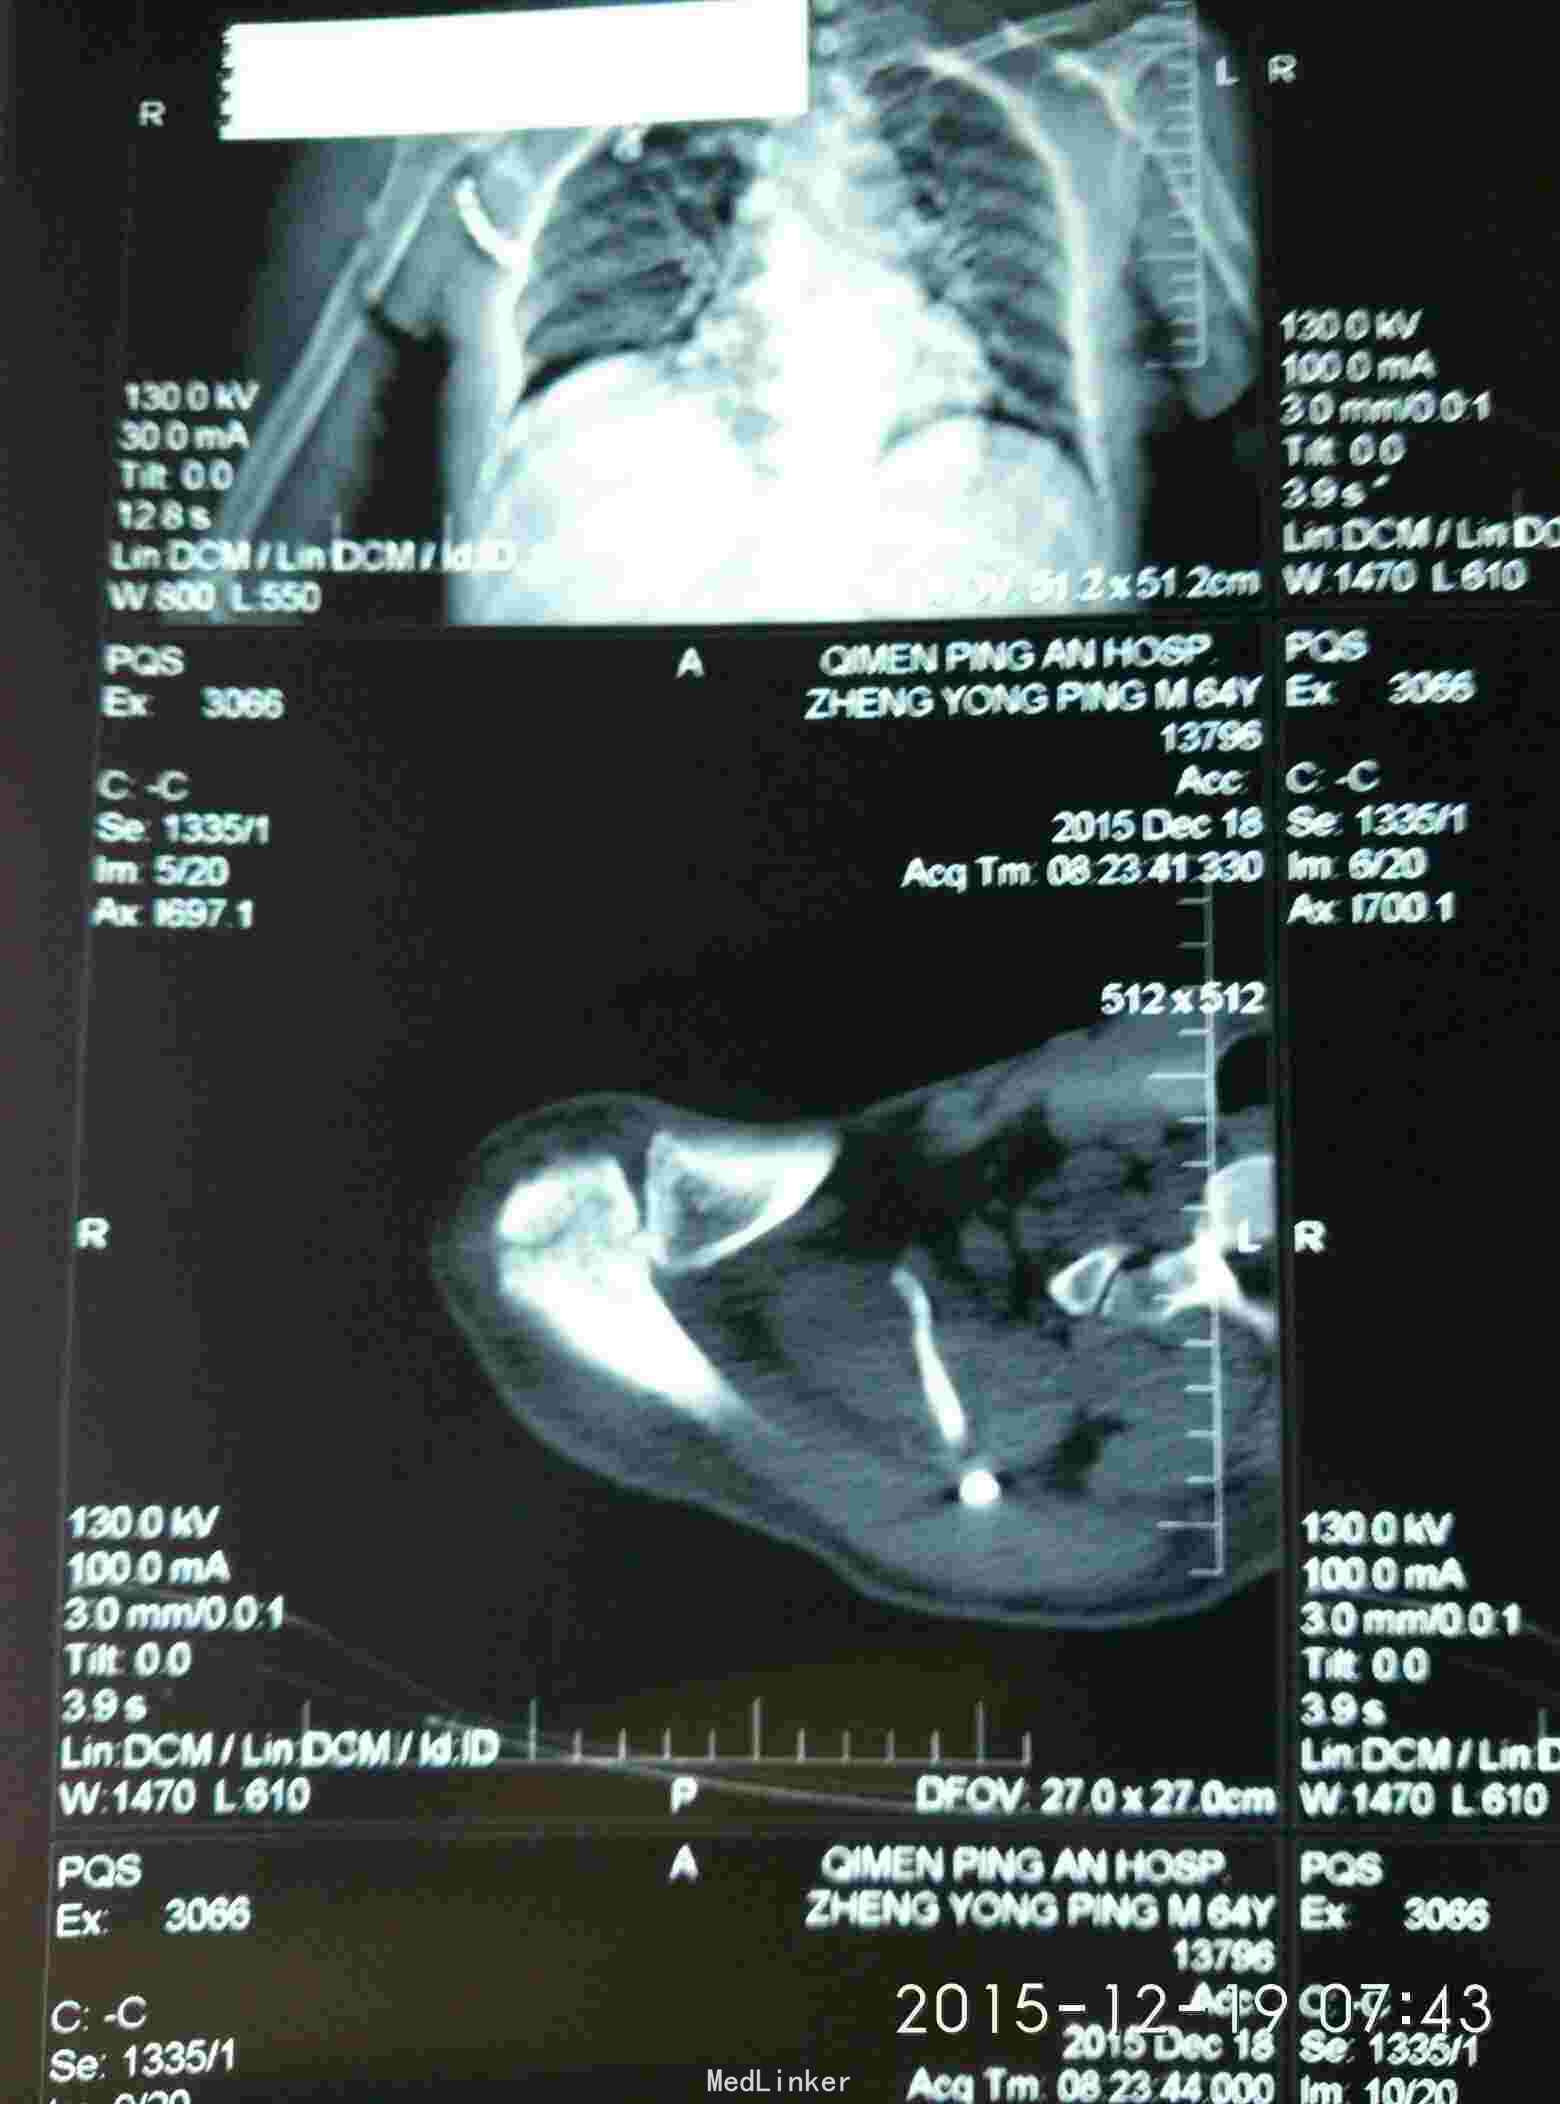

外伤致右胸疼痛及右肩疼痛,活动受限1天入院。去年右肩胛骨骨折在外院行切开复位内固定术。

胸廓挤压试验阳性,右肩峰压痛阳性,右肩主动活动受限,外展约30度。x片及CT示右肩峰骨折及肩胛骨骨折,右第6.7.8.9肋骨骨折。

右肩峰骨折,右肩胛骨骨折,右第6.7.8.9肋骨骨折